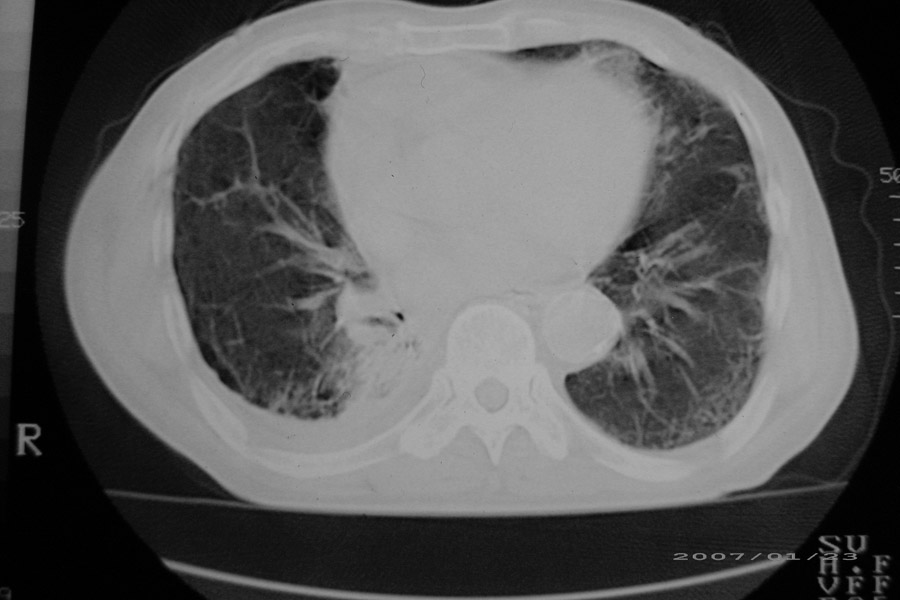

以下是引用天南地北在2007-1-24 18:00:00的发言:[br]1:右下肺内基底段类椭圆性肿快影:考虑1:右下球形肺炎2:右下肺隔离症,建议抗炎治疗后复查。[br]2:右肺及左下肺感染,右侧少量胸腔积液。

以下是引用hhcckk在2007-1-24 18:11:00的发言:[br]病灶周围胸膜反应比较明显,考虑炎症可能性大点,病人年龄较大,病灶成块状,肿瘤也不能排除,可可西里老师看片子的确很仔细,隔离肺暂时我觉得证据的说服力不大,上下层面显示条状影范围较长,可能是增厚的胸膜,可以做个增强鉴别一下